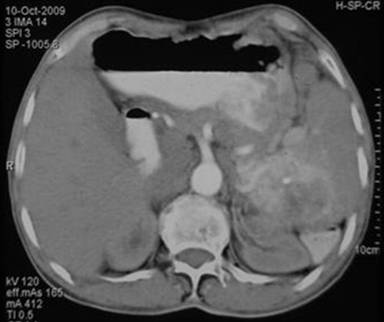

A-75-year old male presented as an outpatient in our department with a history of 2-3 episodes of hematemesis and small amounts of melena. His vital parameters were stable. He did not require any transfusion or hospitalization or had he had any past history of major illness. The patient had no history of alcoholism. Esophagogastroduodenoscopy revealed isolated gastric varices in the fundus. A heterogeneous mass of 4.5x4.3 cm in the spleen with marked vascularity was revealed at ultrasonography. Hence, a CT scan was advised. The CT scan demonstrated a 4.5x4.3 cm heterogeneously enhancing mass mainly in the splenic hilum and the tail of the pancreas with marked vascularity. The mass showed focal calcification with involvement of the splenic vein (Figure 1). There was no evidence of distant metastasis and no evidence of abdominal lymphadenopathy. The pre-operative diagnosis was primary splenic neoplasm (angiosarcoma) or a pancreatic tail tumor.

Figure1. Postcontrast axial CT scan in the arterial phase showing a solitary large contrast-enhanced lesion in the spleen. |